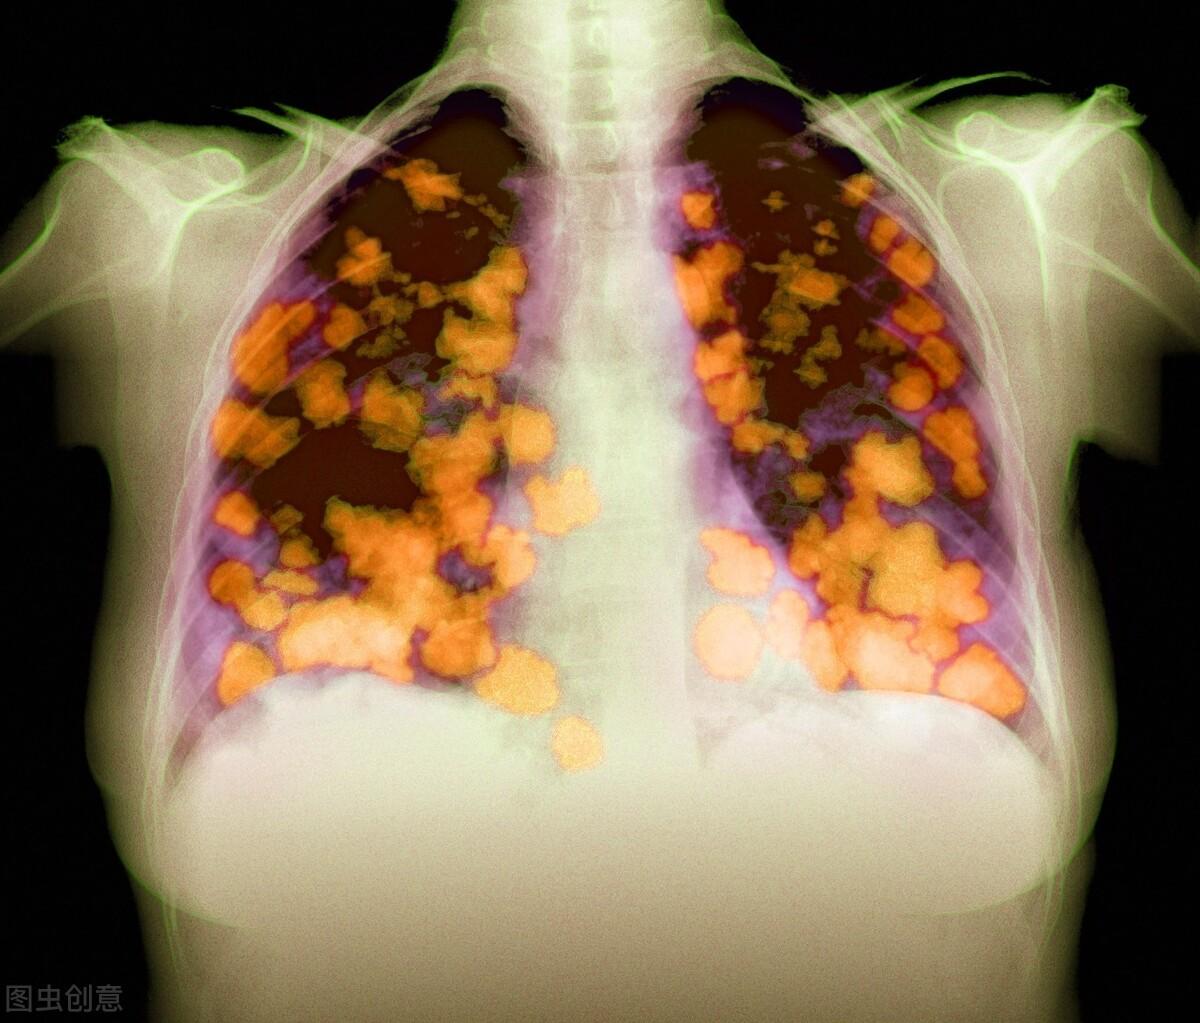

⑦肺癌

硼中子俘获疗法可以治疗哪些肿瘤

适合多种癌症,晚期复发类癌症同样可以适用。